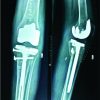

sMCL was assessed in coronal plane, and the proximal attachment (approximately 12 mm from joint line) was observed whether attached or detached (Fig. 1).